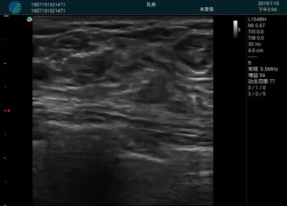

可視化穿刺引導(dǎo)

M20實(shí)時(shí)引導(dǎo):向包塊后方間隙注射利多卡因

清晰顯示腺體內(nèi)低回聲快影,邊界清晰,包膜較光滑

確定進(jìn)針路徑并實(shí)時(shí)監(jiān)測(cè)抽吸針與腫塊位置關(guān)系

抽吸針進(jìn)入腫塊內(nèi)部進(jìn)行旋切

抽吸過(guò)程中可見(jiàn)腫塊明顯縮小,并根據(jù)腫塊位置改變針道位置

抽吸旋切后再進(jìn)行超聲復(fù)查,原腫塊區(qū)域未見(jiàn)殘留組織及出血

超聲引導(dǎo)下抽吸旋切取出的腫塊組織